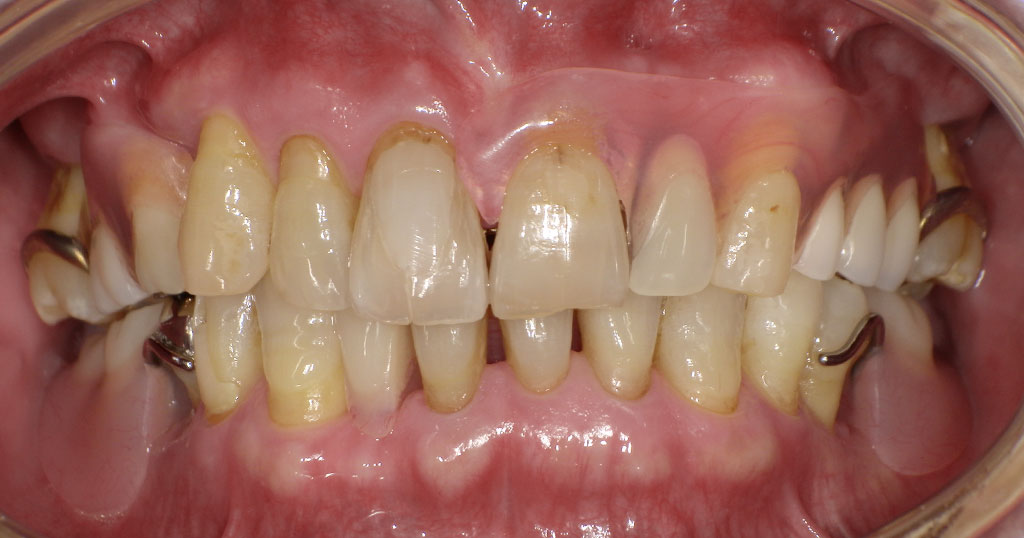

【入れ歯(義歯)症例7】70代男性

70代男性。クラスプの金属が見えないタイプの入れ歯です。有名なスマイルデンチャーSing(三和デンタル社製)異物感の少ない入れ歯です。

Before1

70代男性。上顎右6番左2456番が欠損した状態で来院。今まで使用していた保険の入れ歯を使用しているが滑舌が悪く不満があるため、インプラント手術も怖いということで自費の入れ歯をご希望とのこと。下顎の入れ歯については以前から使用していたもので問題ないとのこと。